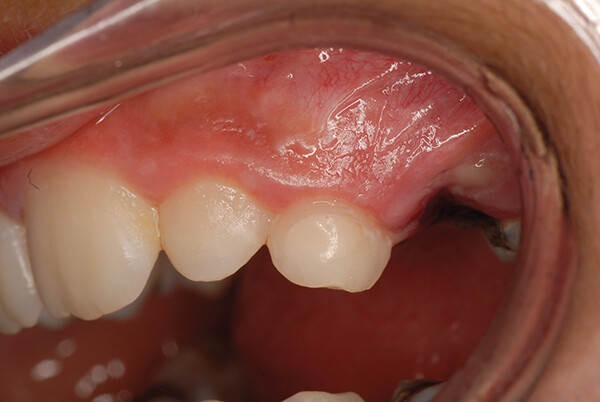

Случай 3: EQUIA Forte HT на зубе № 4 DO

EQUIA Forte HT также является подходящим реставрационным материалом для постоянных зубов. В данном случае зуб № 4 был обработан дистально-окклюзионной (DO) щелевой препаровкой (рис. 7). EQUIA Forte HT Fil был смешан, установлен и контурирован, а EQUIA Forte Coat был нанесен и светоотвержден (рис. 8). Отличное совпадение цвета и способность материала принимать цвет структуры зуба вокруг него были очевидны.